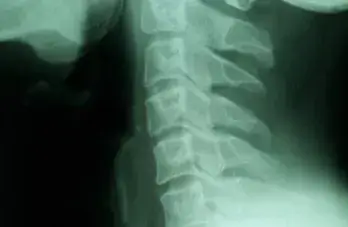

Barium Swallow

Bleeding Polypus Nose

Chicken Bone Nasopharynx

Conductive HL Audiogram

Endoscopic Ear Visualisation

Large Central Perforation

Mastoidectomy

Oropharyngeal Rhinosporidiosis

Tonsillitis

Fb Cricopharynx

Haller Cell

Inverted Papilloma Nose

Mastoidectomy 2

Mastoidectomy Cavity

Nasal Rhinosporidiosis

Neck Abscess

Palatal Ulcer

Retropharyngeal Abscess